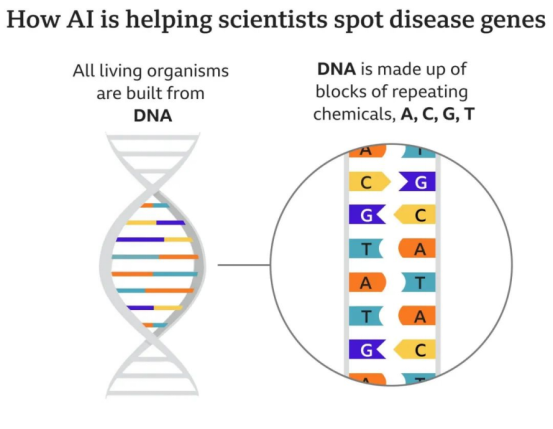

在精准医疗方面,AI 可以通过对基因组、表观遗传组、转录组等大规模生物数据进行挖掘和分析,为个体化的预防、诊断和治疗提供依据。例如,Deep Genomics的 AI 平台可以预测基因变异对蛋白质功能和表型的影响,Flatiron Health的 AI 平台可以利用实时临床数据为癌症患者提供最佳治疗方案。

例如,专注疾病基因搜索的谷歌DeepMind团队,就通过人工智能系统,解析出了人体中几乎所有蛋白质的结构。

这样一来,AJ就可以判断DNA中的字母是否会产生正确的结构。如果不是,它将被列为潜在的致病因素。